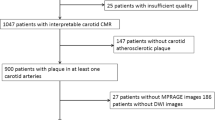

Of the 3061 patients with acute ischemic stroke between January 2013 and December 2017, 657 (21.5%) were classified as having large artery atherosclerosis according to the TOAST classification. Among the latter, 117 (17.8%) patients had symptomatic pICA disease. After excluding patients with complete occlusion of the carotid artery, those with no DWI or MRA data, and those with poor MRA quality, the final study population included 93 patients.